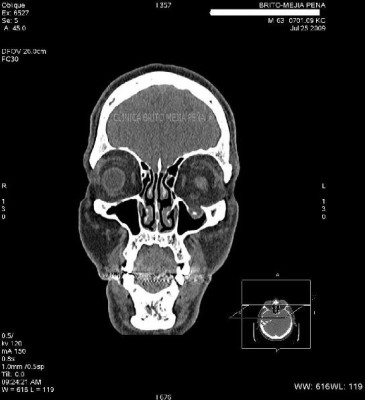

Fístula LCR coronal